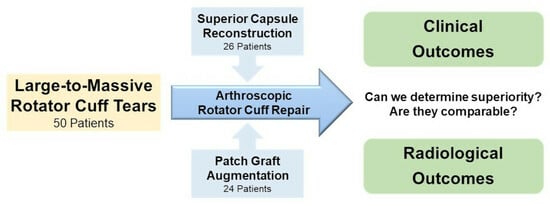

2.5. Surgical Technique

2.5.1. Preparation Procedure

2.5.2. Superior Capsule Reconstruction

2.5.3. Patch Graft Augmentation